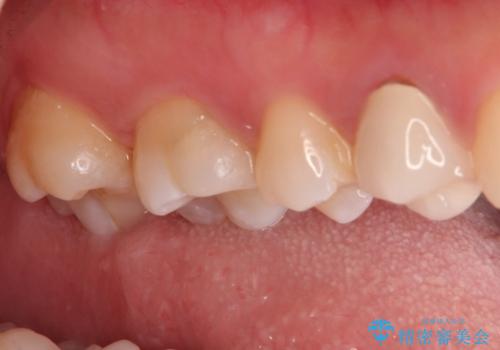

【VPT(歯髄温存療法)とセラミックインレー】深い虫歯でも神経を残したい

- 虫歯が大きく神経まで達していたので、VPT(歯髄温存療法)を行って細菌感染した部分の神経のみ取り除き、保存可能な神経は保存し被せ物はセラミックインレーで治療を行いました。